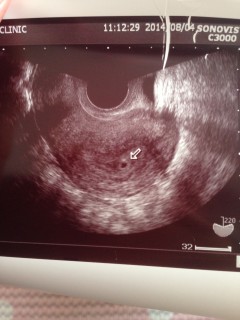

先週ほんの小さな黒い丸が見えましたが、今週また確認すると、真ん中らへんに0.5cmと0.6cmの二つの胎のうが確認されて、二卵性双生児という事がわかりました!ビックリです!!初産で、不安もいっぱいですが楽しみです(*^^*)